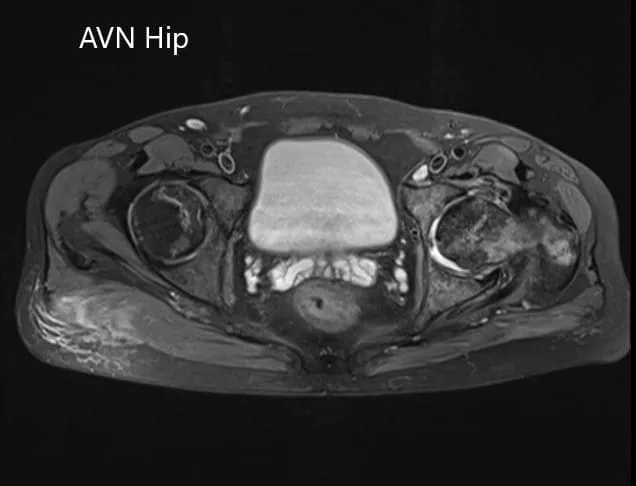

Se realizó una resonancia magnética de la pelvis que sugirió una disminución de la intensidad de la señal tanto en T1WI como en T2WI sugiriendo esclerosis y edema periarticular. Hubo un colapso de la cabeza del fémur. Las características sugerían necrosis avascular avanzada de la articulación de la cadera izquierda.

Sección axial del T2WI de la pelvis